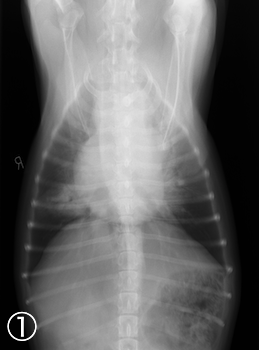

・頭部・胸部・腹部レントゲン検査

・胸部エコー検査・・・弁膜症、心筋症、先天性心疾患の有無など

<検査結果見本>

・胸部レントゲン検査

・心臓超音波検査